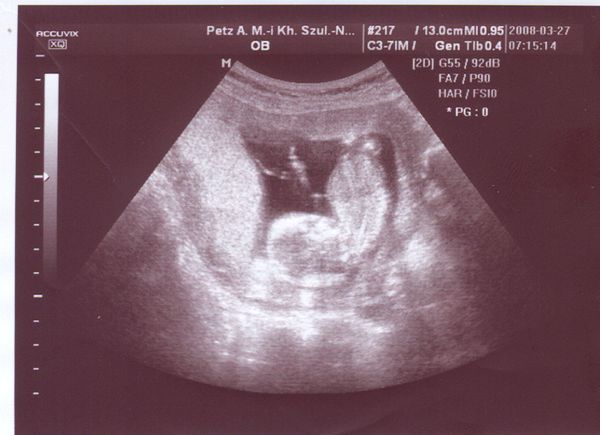

Köszönöm az aggódást és a drukkokat! Jól vagyunk. Kedden voltam 12 hetes vizsgálaton. Babával minden OK. Haematoma még megvan, de már csak barnázás várható (ami szerdától péntekig volt is), de a babára már nem jelent veszélyt. Amnio április 21-én lesz.